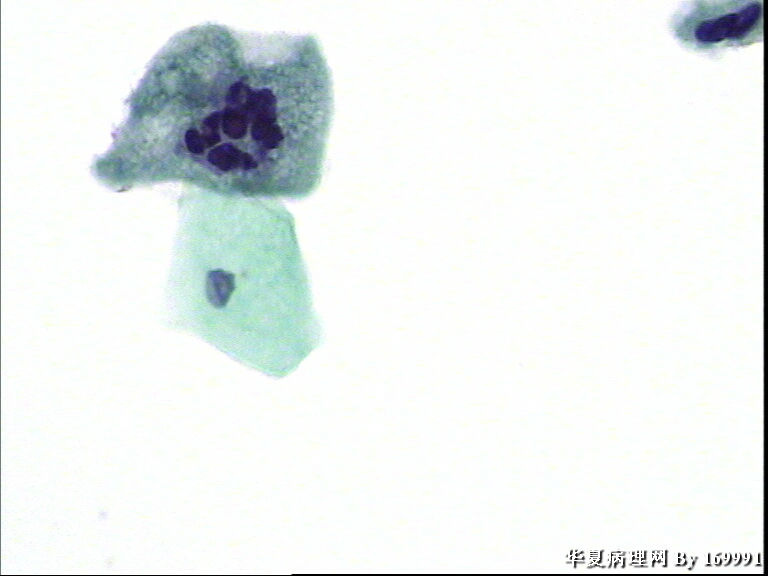

宫颈液基,患者,23岁,宫颈中糜

• 宫颈液基,患者,23岁,宫颈中糜图1

图1